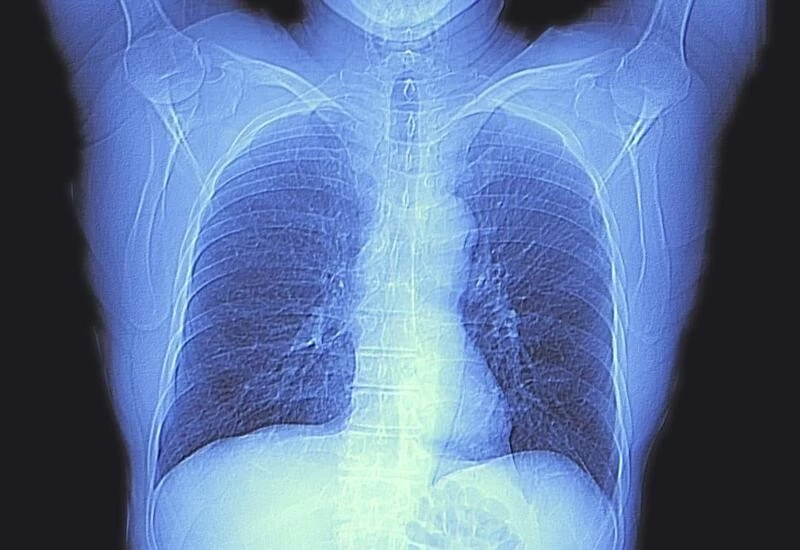

New Delhi: A 12-year-old Kolkata boy was brought to the hospital after he complained of severe cough. Doctors suspected there must be some foreign body inside his lungs and a CT scan was done. By foreign body, the doctors didn’t anticipate what they found in the scan: a pan cap. The boy’s family members said that he had swallowed a pen cap in November.

“After the CT scan revealed that a pen cap was inside his left lung, a bronchoscopy was done on Thursday and it was removed. He is stable and out of danger,” Dr Sengupta said.